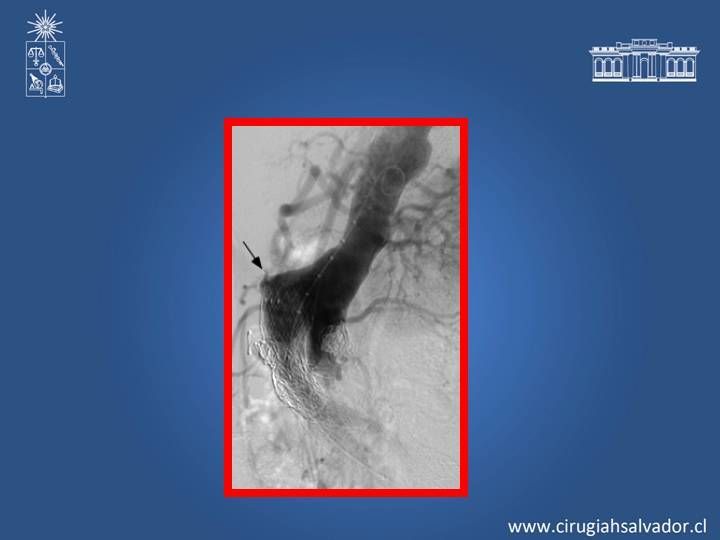

Complicaciones de EVAR

Vascular

| Autor: Dr. Roberto Macchiavello